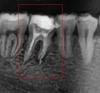

securos Опубликовано 20 марта, 2011 Поделиться Опубликовано 20 марта, 2011 В пятницу запломбировали каналы зуба.... до сих пор ноет аж на стену лезу по снимку мне все нормально запломбировали? зуб выделен в красный квадрат Ссылка на комментарий

DokDent Опубликовано 22 марта, 2011 Поделиться Опубликовано 22 марта, 2011 Что конкретно не так? можете объяснить? Плохо запломбированы каналы.(не на всём протяжении,недостаточно расширены).Возможно пропущен ещё один канал. Ссылка на комментарий

zybnaya feya Опубликовано 22 марта, 2011 Поделиться Опубликовано 22 марта, 2011 Каналы необходимо перелечить. Ссылка на комментарий

juli63 Опубликовано 22 марта, 2011 Поделиться Опубликовано 22 марта, 2011 или зуб потеряете... Ссылка на комментарий